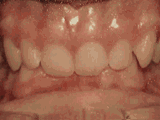

爱美之心,人皆有之~~5月份世界正畸日即将来临,暑假还远吗?分院提前给爱美的你准备好一份大大的福利,还等什么呢?抓紧约起来吧! 发现自己牙齿不整齐影响交际, 怎么还能与小伙伴愉快地玩耍? 无论是即将迈入新的年级还是即将面临找工作, 发现自己是“地包天”“龅牙妹”, 分分钟拉远自己和同龄人的距离! 这些难以启齿的牙齿问题, 想想就让人心碎,怎么办呢? 不要着急,不要慌乱! 这个时候, 你可能需要的就是牙齿矫正了~! 以下图片告诉你, 这些情况都适合去做牙齿矫正哦~! 前牙移位 症状表现:牙齿缺失、牙周疾病等导致相邻牙齿无秩序前突 牙列拥挤 症状表现:牙齿过多,牙槽骨过窄,使牙齿没有足够空间生长造成牙齿排列不齐 开颌 症状表现:通俗来讲就是咬牙时无法紧闭,上下牙齿中间有缝 上牙深覆合 症状表现:上牙边沿覆盖下牙超过1/3,俗话说的天包地 后天牙列稀疏 症状表现:疾病外因等造成的牙列稀疏,牙槽骨过长或牙齿缺失,导致排列太宽松,零零散散 前牙反合 症状表现:下牙边沿覆盖上牙超过1/3,俗话说的地包天 天生牙列稀疏 症状表现:天生的牙列稀疏,牙槽骨过长,牙缝过宽、牙齿较少(一般不缺牙),导致排列宽松,零零散散 以上几种情况有你么? 要知道一口整齐的牙齿 绝对能够把整体的颜值提升N个档次! 如果你不幸中招, 就好好利用这个正畸月, 来分院加入到正畸大军里吧! 牙齿正畸也叫做牙齿矫正,原理简单来讲呢,就是对牙齿施加一个合适的外力(一般通过矫正器来施加),这个力会通过牙齿传递到牙齿周围的牙槽骨上,使得代谢很活跃的牙槽骨发生改建,从而带动牙齿一起缓慢移动。其治疗效果有着肉眼可见的强大变化! 借此正畸月,分院为大家准备了正畸月大放价,暑假提前约的活动!!!如果还想了解更多关于牙齿矫正的信息,欢迎大家来到分院进行咨询哦~我们的专业团队会帮您定制最适合自己的矫正方案,活动月矫正方案免费送哦!定能助您改“斜”归“正”!露出灿烂自信的笑容!